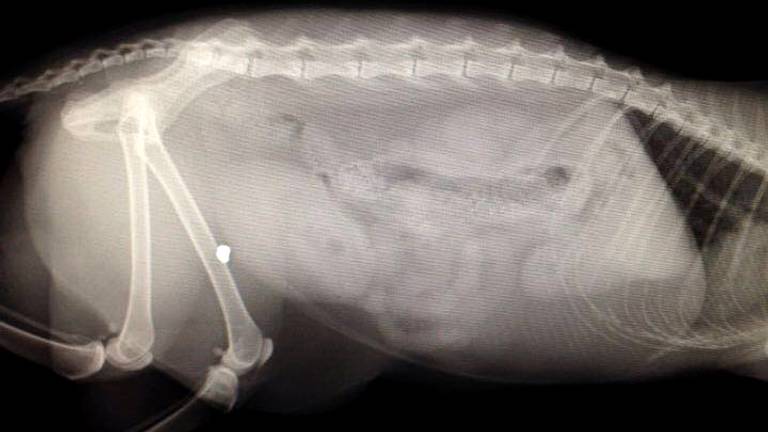

1/2 De kogelwond (foto: Dierenkliniek Maaspoort)

Uit een röntgenfoto bleek dat er een kogeltje in Pluk zit, dat afkomstig is van een luchtbuks. Waar de kat precies beschoten is, is niet duidelijk. "Het dier kwam zo thuis", legt een medewerker van Dierenkliniek Maaspoort uit.

Niet in botVoor Pluk valt het uiteindelijk allemaal mee. "De kogel zit gelukkig niet in z'n bot. Vermoedelijk zal de kat helemaal herstellen."